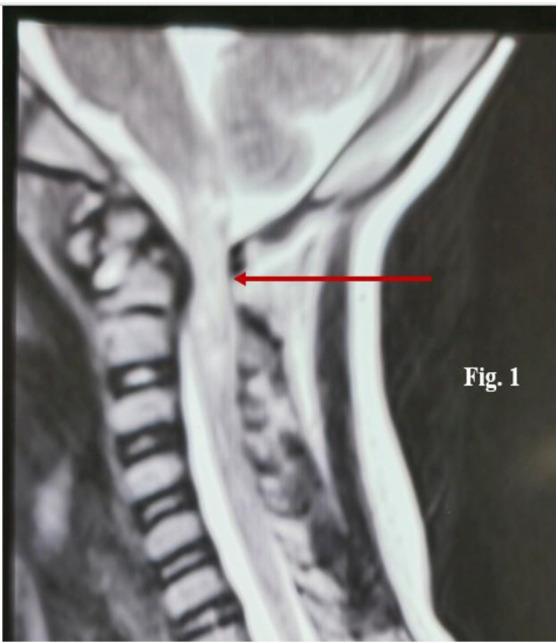

Severe Respiratory Acidosis-induced Involuntary Hyper defecation: The Role of Medullary Caudal Raphe Nuclei.

Niger Med J. 2025 Jan 10;65(6):1194-1196. doi: 10.60787/nmj.v65i6.665. eCollection 2024 Nov-Dec.

DOI:10.60787/nmj.v65i6.665

PMID:39877514

原文链接:https://pmc.ncbi.nlm.nih.gov/articles/PMC11770658/